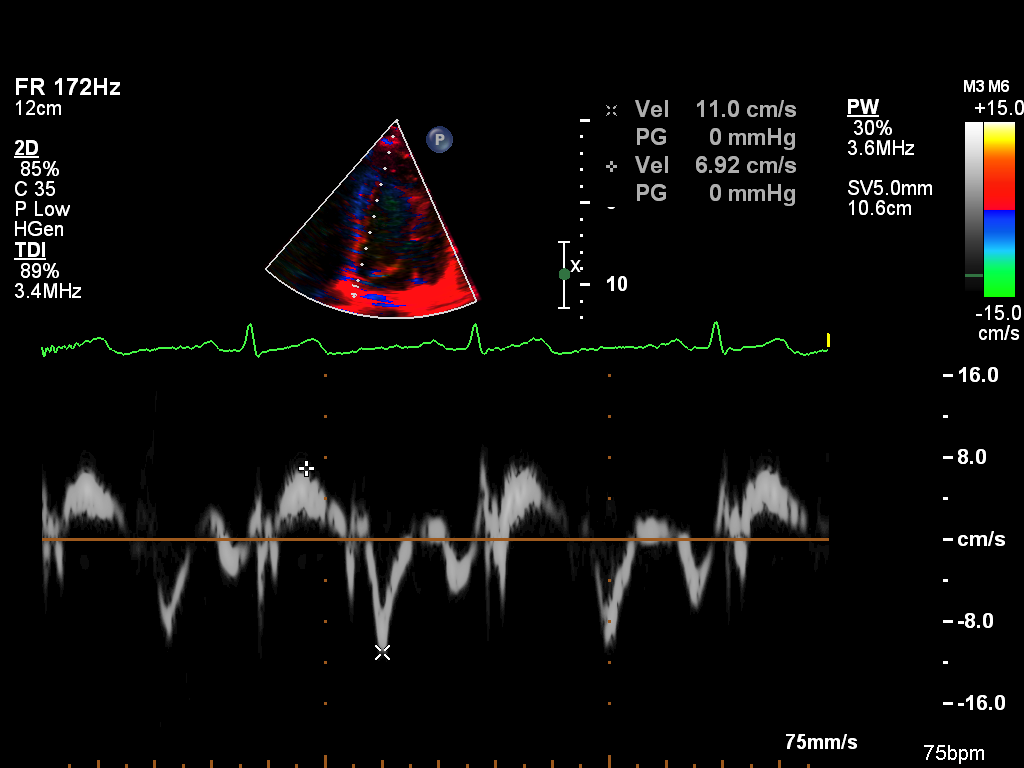

Doppler (8 views)

ImageView NameDescription

doppler-tissue-lateral doppler-tissue-lateral Tissue Doppler of the LV lateral wall

doppler-tissue-rv doppler-tissue-rv Tissue Doppler of the RV free wall

doppler-tissue-septal doppler-tissue-septal Tissue Doppler of the LV septal wall